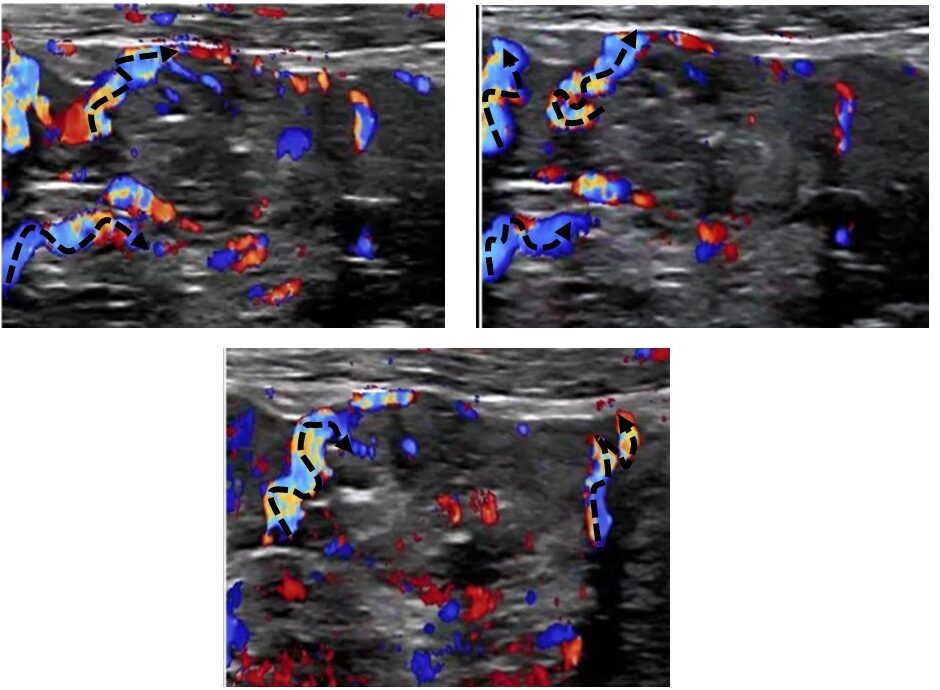

The thickened wall was significantly hyperperfused. Winding mesenteric veins could be seen running towards the thickened bowel loop.

Winding mesentric veins (dashed arrows) running towards a thickend painful jejunal loop

The tortuous distension of the small jejunal branches of the first jejunal vein [1] resulting in a pronounced venous marking of the thickened bowel wall was likely due to soft venous walls, distending under the recurrent frequent pressure changes during daily life while changing body posture from lying to standing or sitting. This transformed these veins which had all the characteristics of varicose veins (tortuous course, changing diameter, bud- like protrusions).

In contrast to inflammatory hyperperfusion, where only tiny veins inside the bowel wall are distended, here, larger veins in the mesentery also showed distension and winding, indicating gravitational congestion, comparable to varicose veins in the legs in some patients .

An obvious differential diagnosis of a hyperperfused and thickened jejunal wall would be a chronic inflammatory bowel disease. However, while inflammation is characterised by numerical increase of multiple small vessels restricted to the mucosa or submucosa of the small bowel, this patient exhibited in addition large winding vessels within the mesentery , indicating distension of the veins inside the mesentery and bowel wall due to orthostatic distension caused by congestion.